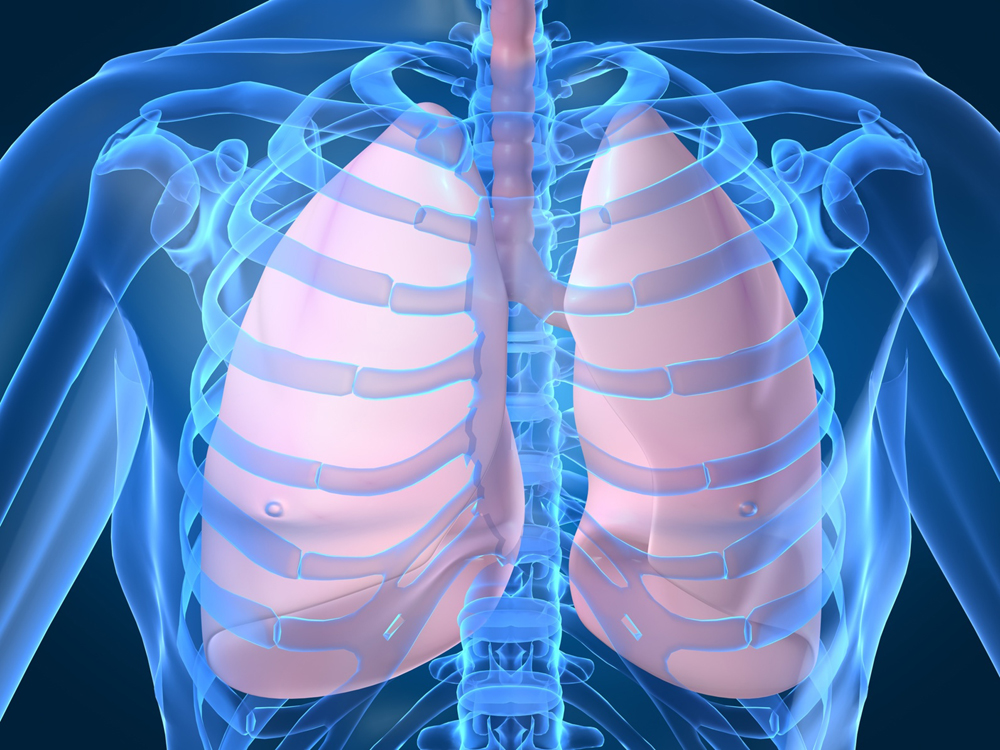

Здоровье дыхательной системы: бронхи и легкие